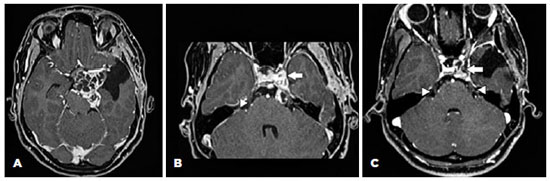

An 18-year-old female patient presented with left ptosis and exotropia after resection of a cavernous sinus schwannoma 15 months previously. Figure 1 (A and B) shows the lesion when she was referred to our service, after a prior surgery in another hospital. Figure 1C shows the postoperative aspect. Her past ocular history was unremarkable. Cranial nerve assessment revealed hypoesthesia in the left hemiface without facial weakness.